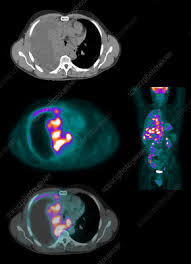

Lung Cancer With Malignant Mesothelioma : Malignant Mesothelioma Keyword Search Science Photo Library : 02.04.2020 · malignant mesothelioma is a rare and aggressive cancer.. 01.01.2019 · a study investigating patients with malignant mesothelioma showed that the complication of lung cancer was detected in only 6 of 500 patients (1.2%). Malignant mesothelioma is not the same as lung cancer. 02.04.2020 · malignant mesothelioma is a rare and aggressive cancer. 12.09.2021 · the research was presented today at the iaslc 2021 world conference on lung cancer in oa13: A study of 2,804 patients with stage i …

12.09.2021 · the research was presented today at the iaslc 2021 world conference on lung cancer in oa13: 01.01.2019 · a study investigating patients with malignant mesothelioma showed that the complication of lung cancer was detected in only 6 of 500 patients (1.2%). There are different types of mesothelioma, including pleural and peritoneal mesothelioma. A study of 2,804 patients with stage i … Malignant mesothelioma is not the same as lung cancer. 02.04.2020 · malignant mesothelioma is a rare and aggressive cancer.